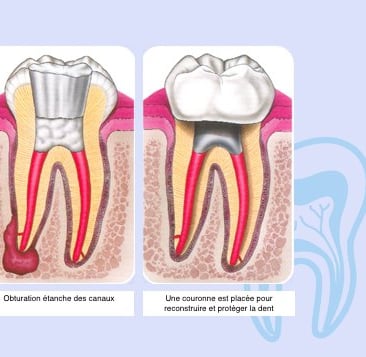

Au cours de ce traitement, l’ensemble des canaux sont nettoyés, désinfectés et enfin obturés afin d’éviter toute réinfection.

Une fois que le traitement endodontique est réalisé, il est impératif de restaurer rapidement la partie abimer de la dent par votre praticien traitant, afin d’une part de prévenir la réapparition de bactéries dans les canaux, et d’autre part de consolider la dent pour éviter qu’elle ne se fracture . En fonction de son délabrement votre dent sera reconstituée par votre praticien soit par un composite, un inlay, un onlay ou une couronne prothétique. Pour suivre et contrôler le processus de cicatrisation, des contrôles radiographiques peuvent s’avérer nécessaire.